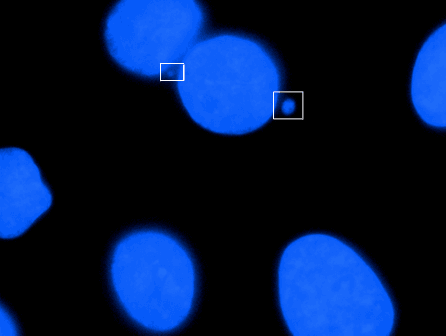

Micronucleus is the name given to the small nucleus that forms whenever a chromosome or a fragment of a chromosome is not incorporated into one of the daughter nuclei during cell division. It usually is a sign of genotoxic events and chromosomal instability. Micronuclei are commonly seen in cancerous cells and may indicate genomic damage events that can increase the risk of developmental or degenerative diseases. Micronuclei form during anaphase from lagging acentric chromosome or chromatid fragments caused by incorrectly repaired or unrepaired DNA breaks or by nondisjunction of chromosomes. This incorrect segregation of chromosomes may result from hypomethylation of repeat sequences present in pericentromeric DNA, irregularities in kinetochore proteins or their assembly, dysfunctional spindle apparatus, or flawed anaphase checkpoint genes. Micronuclei can contribute to genome instability by promoting a catastrophic mutational event called chromothripsis. Many micronucleus assays have been developed to test for the presence of these structures and determine their frequency in cells exposed to certain chemicals or subjected to stressful conditions. The term micronucleus may also refer to the smaller nucleus in ciliate protozoans, such as the Paramecium. In mitosis it divides by fission, and in conjugation a pair of gamete micronuclei undergo reciprocal fusion to form a zygote nucleus, which gives rise to the macronuclei and micronuclei of the individuals of the next cycle of fission. Micronuclei in newly formed red blood cells in humans are known as Howell-Jolly bodies because these structures were first identified and described in erythrocytes by hematologists William Howell and Justin Jolly. These structures were later found to be associated with deficiencies in vitamins such as folate and B12. The relationship between formation of micronuclei and exposure to environmental factors was first reported in root tip cells exposed to ionizing radiation. Micronucleus induction by a chemical was first reported in Ehrlich ascites tumor cells treated with colchicine.